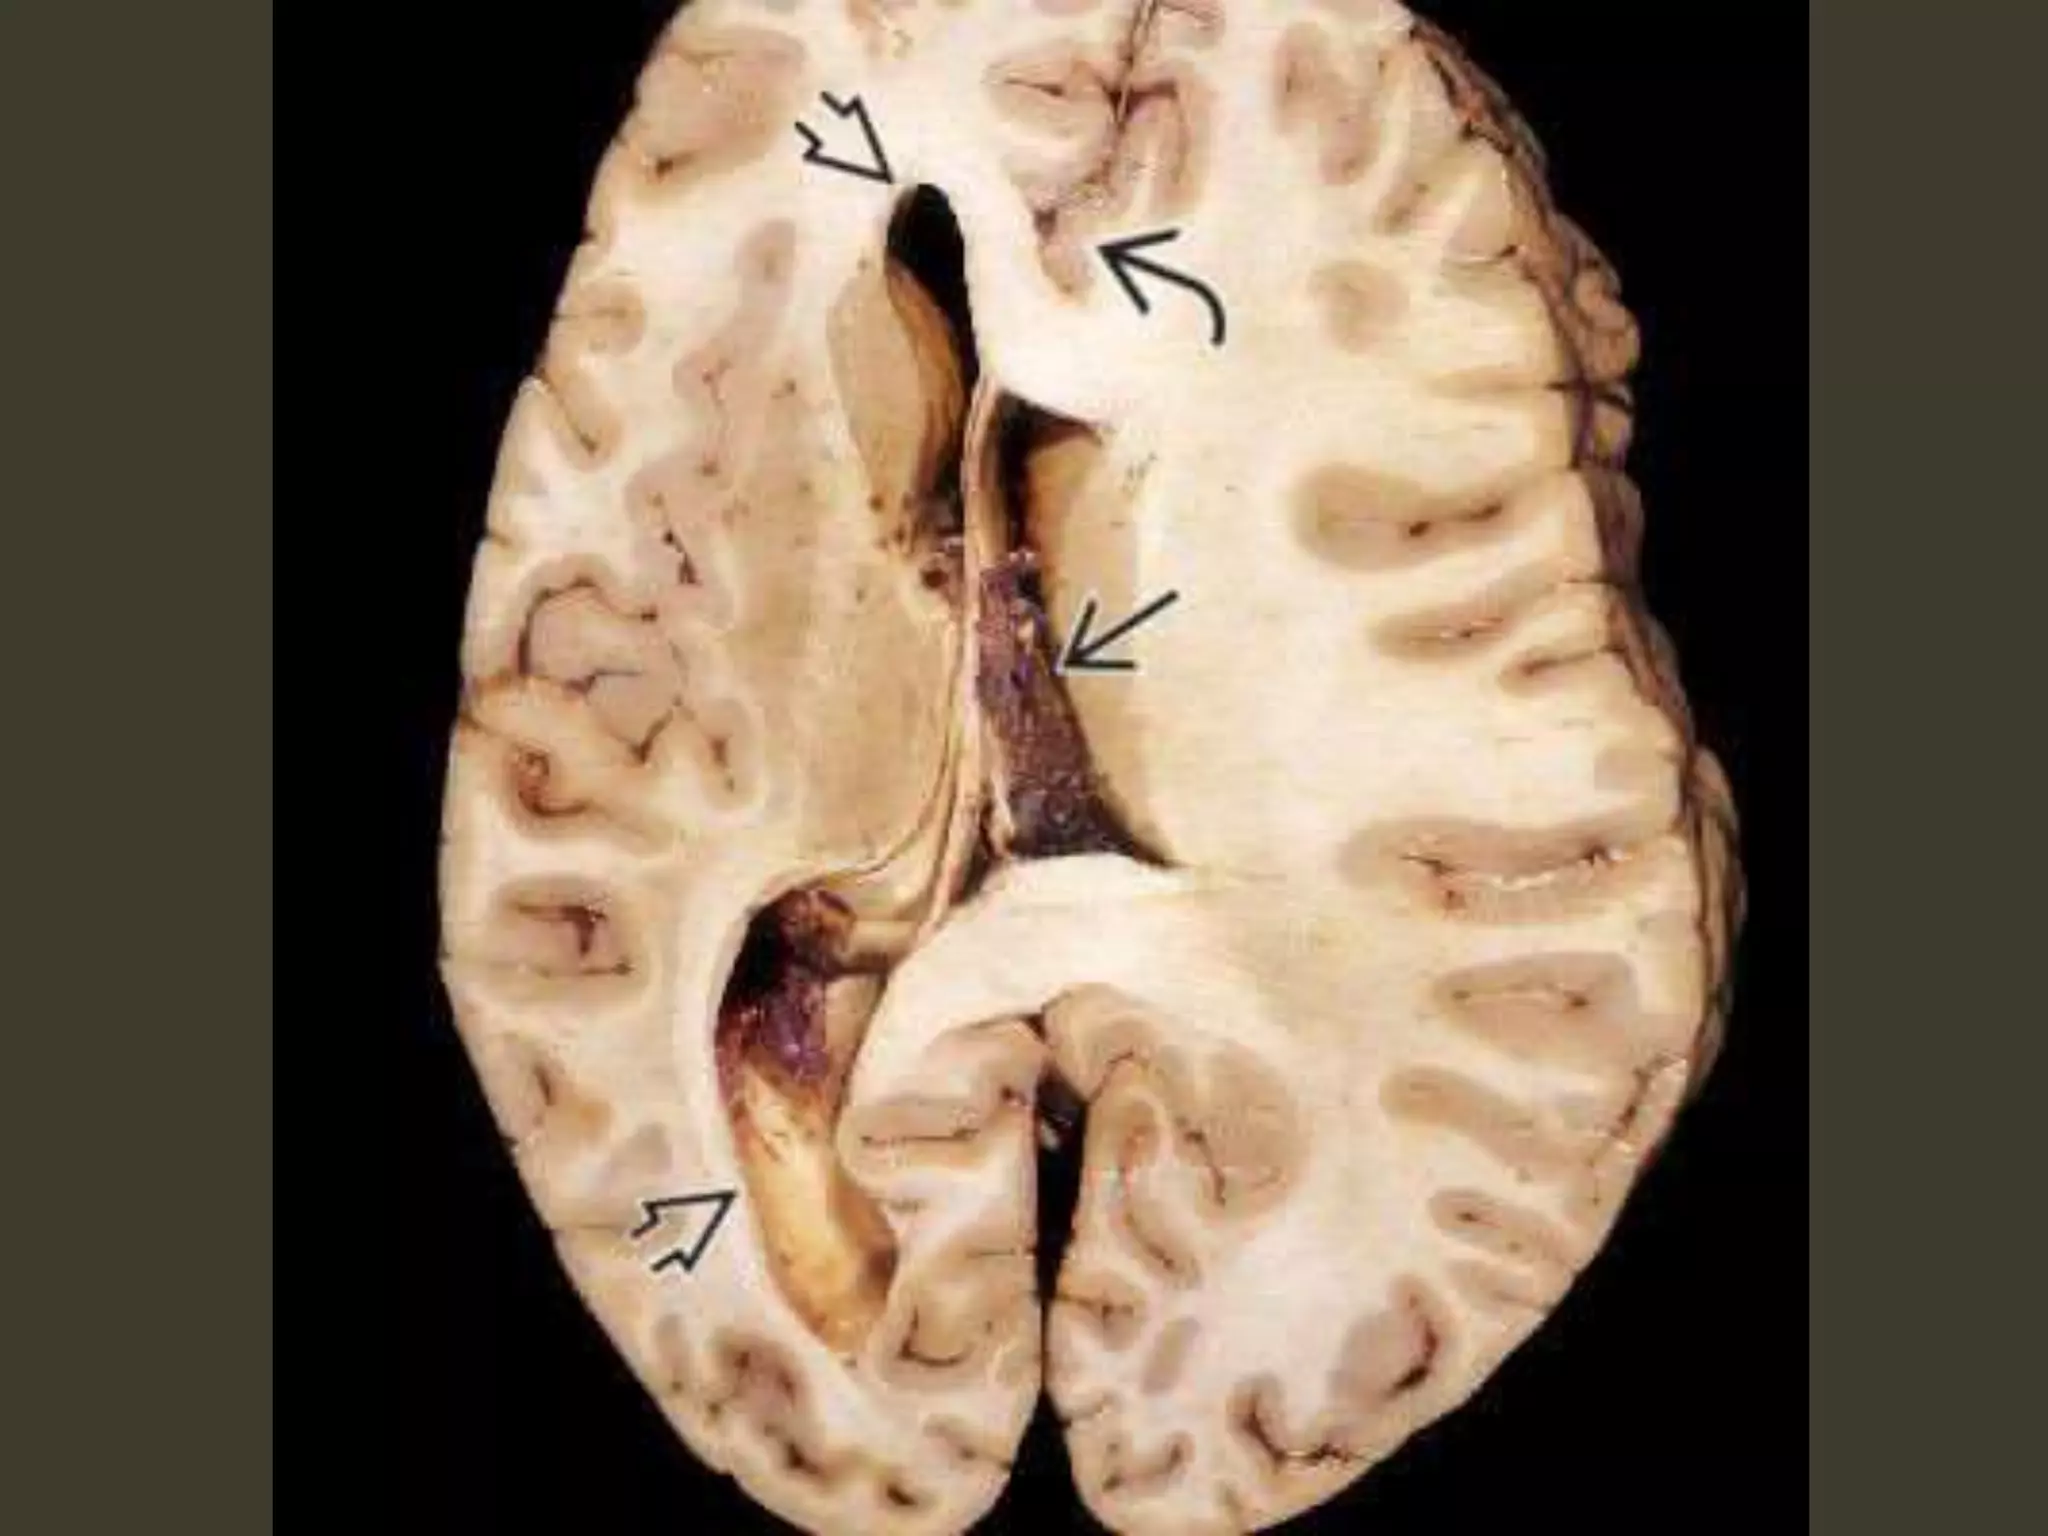

Complete bilateral DTH

both temporal lobes herniate medially into the

tentorial hiatus

midbrain and pons displaced inferiorly through

the tentorial incisura

The angle between the midbrain and pons

is progressively reduced from 90° to almost 0°

Complications

• CN III (oculomotor) nerve compression

– CN III palsy

• PCA occlusion as it passes back up over the

medial edge of the tentorium

– secondary PCA (occipital) infarct

Kernohan notch

• As the herniating temporal lobe pushes the

midbrain toward the opposite side of the

incisura

– contralateral cerebral peduncle is forced

against the hard edge of the tentorium

• Pressure ischemia 🡪 ipsilateral hemiplegia

– the "false localizing" sign

Duret hemorrhage

"Top-down" mass effect displaces the midbrain

inferiorly

closes the midbrain-pontine angle

Perforating arteries from basilar artery

are compressed and buckled

hypothalamic and basal

ganglia infarcts

perforating arteries from the

circle of Willis compression against the

central skull base

hypothalamic and basal ganglia

infarcts